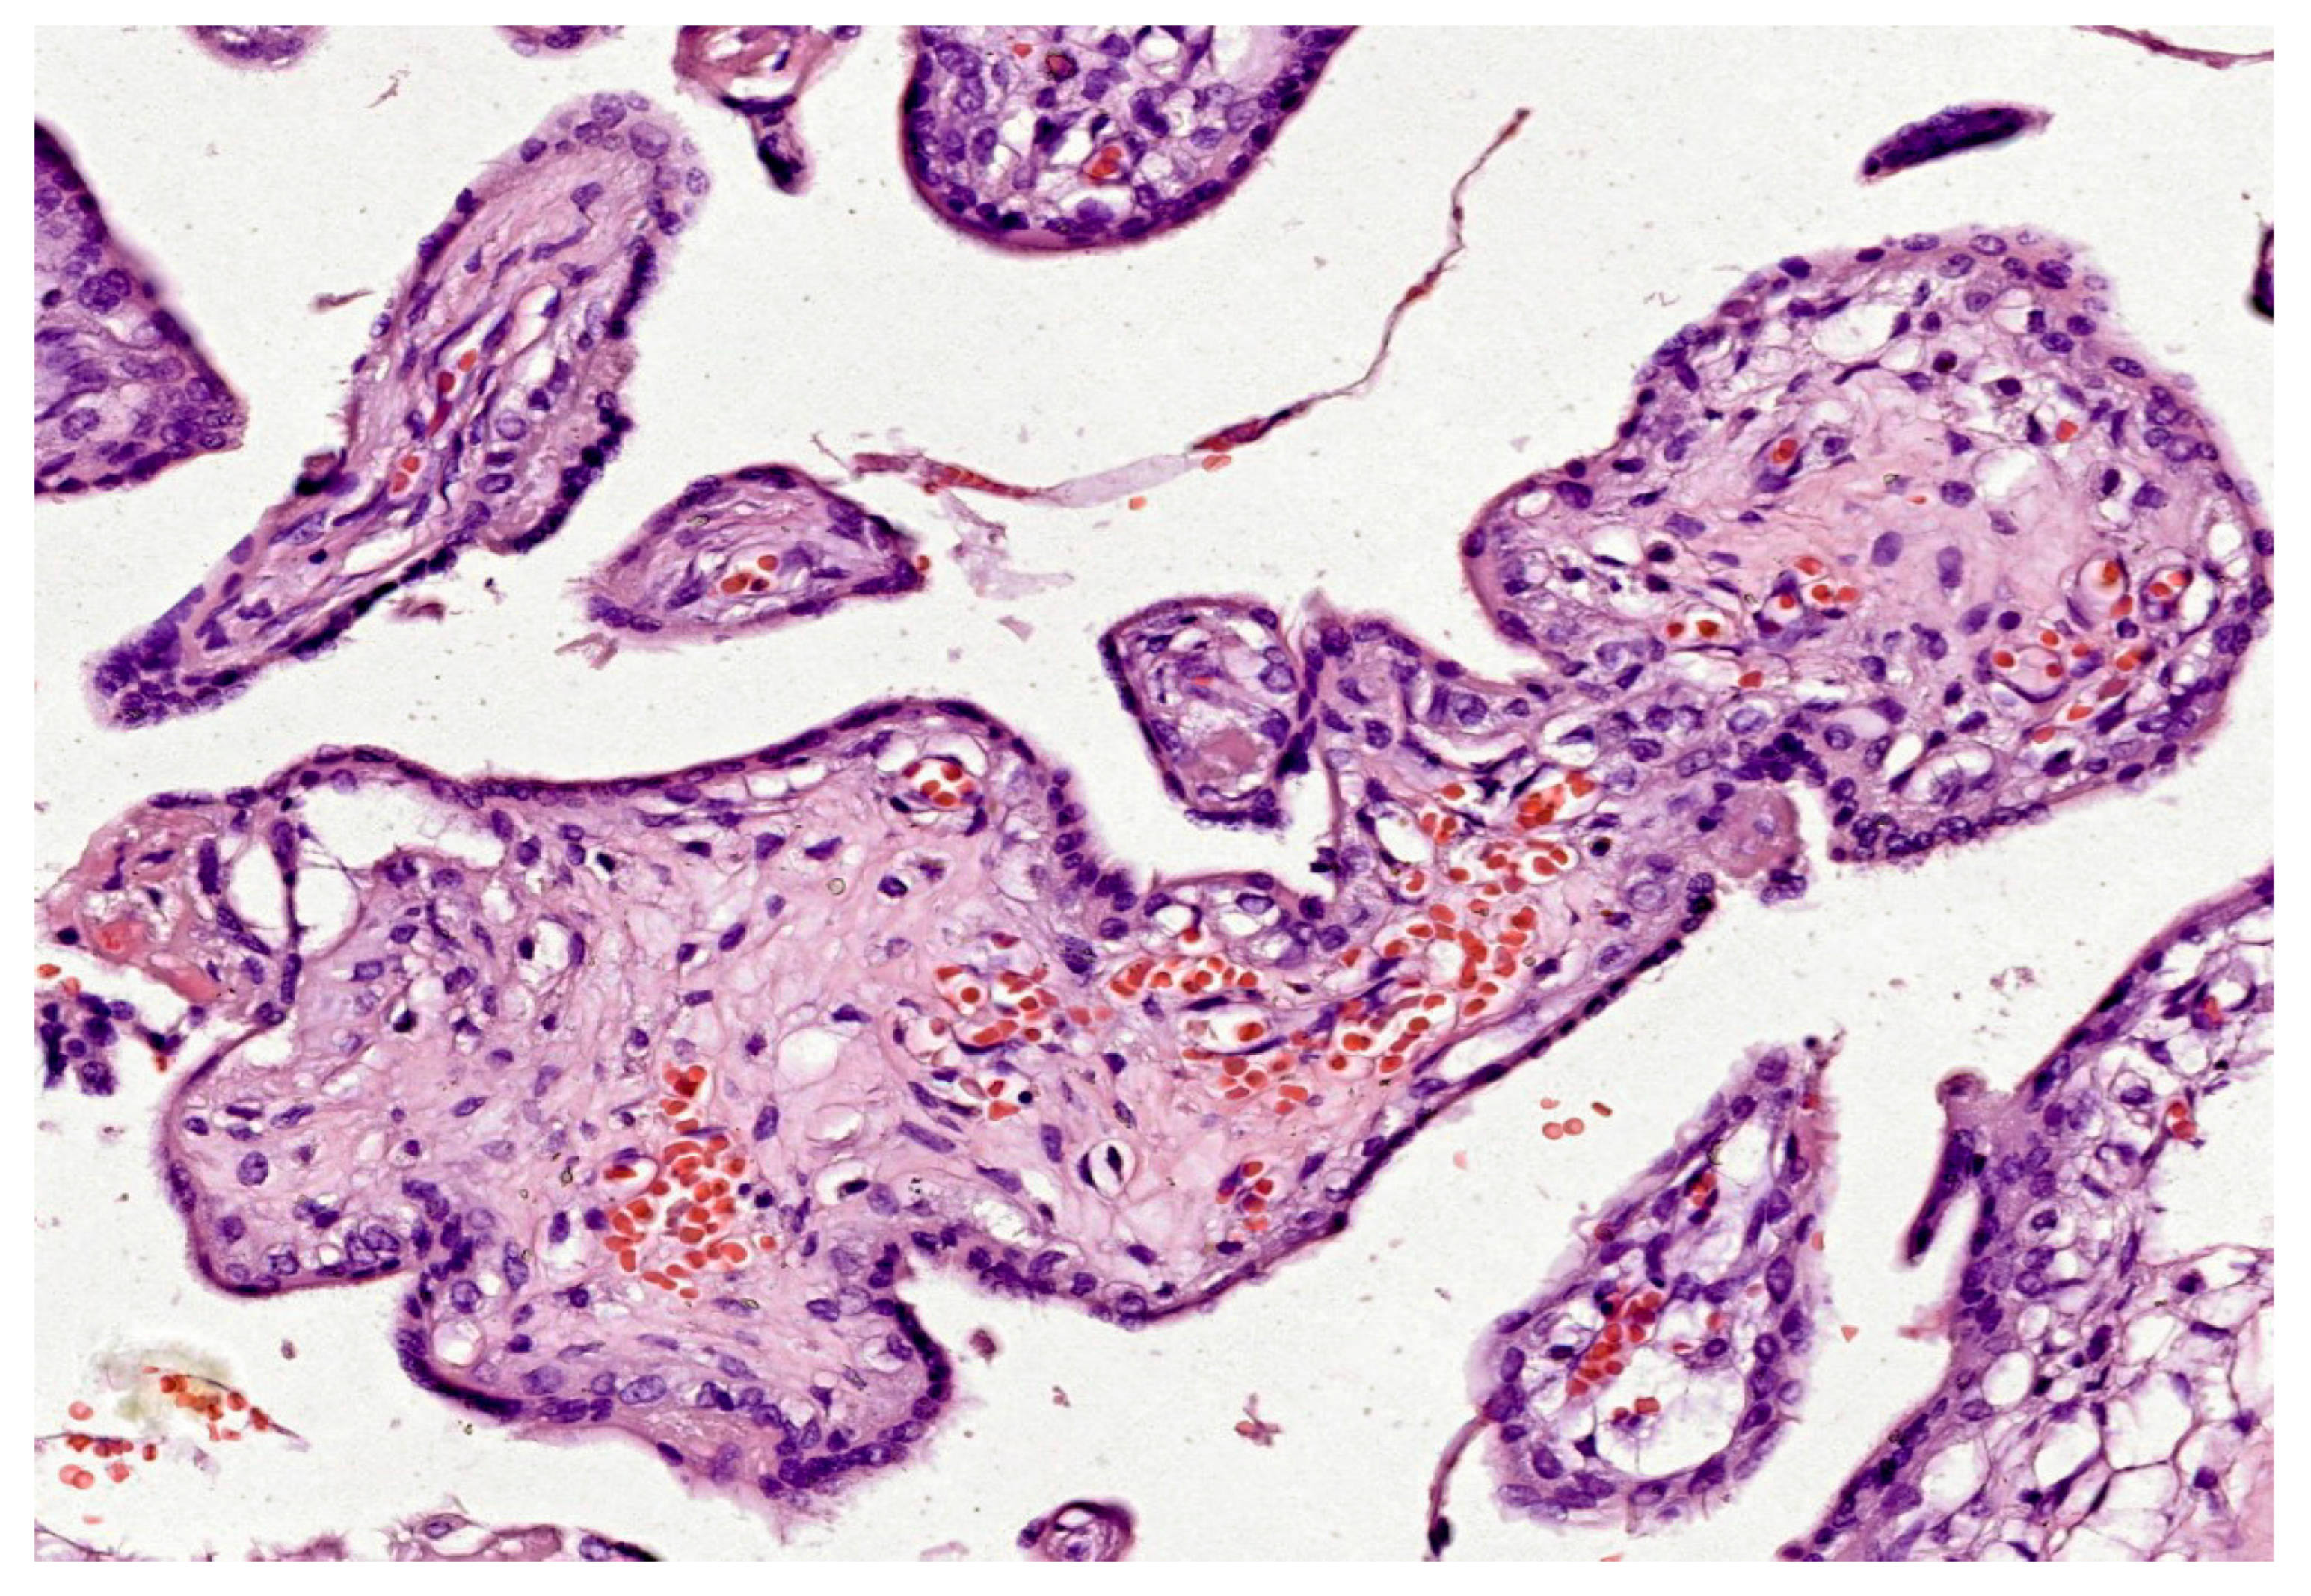

In the first trimester, villi are composed of peripheral syncytiotrophoblast and inner cytotrophoblast layers (see Figure 1). The growth of the villi primarily depends on the proliferative activity of cytotrophoblastic cells. The core of the villi contains mesenchymal tissue, in which blood vessels develop. In addition, trophoblastic columns form in the deeper implantation zone, extending into the maternal decidua along with the syncytiotrophoblast, and are composed of intermediate trophoblasts (also known as “X cells”). Chorionic villi can be classified into three types based on their morphology:

The loose connective tissue in the villous core includes fibroblasts, Hofbauer cells (macrophages), and blood vessels (see Figure 1). Cytotrophoblasts are composed of individual cuboidal cells. The cytotrophoblastic nuclei are round and euchromatic, and their cytoplasm is pale and contains few organelles. Syncytiotrophoblasts are multinucleated and located at the periphery of the trophoblast. The syncytiotrophoblast cells possess numerous microvilli and pinocytotic vesicles; small, hyperchromatic nuclei; and a cytoplasm rich in well-developed rough endoplasmic reticulum, multiple Golgi complexes, mitochondria, and lipid inclusions. Cytotrophoblasts largely disappear in the second half of pregnancy, whereas syncytiotrophoblasts persist until delivery (see Figure 2).